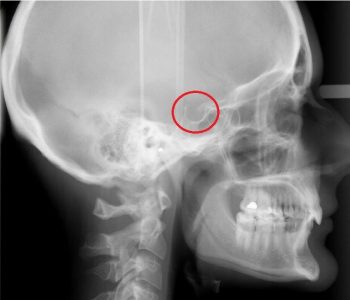

Рентген турецкого седла показания противопоказания методика проведения Автор Екатерина Михайлюк | дата обновления 09.01.2017 Facebook Мой мир Вконтакте Одноклассники Google+ Рубрика: Поделись в соцсетях Вконтакте Facebook Одноклассники Google+